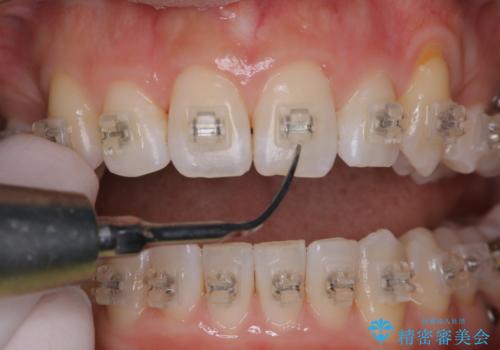

ワイヤー矯正中のPMTC

- ワイヤー矯正中に装置の周りの着色が気になるとのことで来院されました。PMTC30分コースを行いました。

ワイヤー矯正中も、歯の表面に着色(ステイン)が付着することがあります。着色(ステイン)が付着したままだと審美的な問題以外にも、虫歯を発見しずらいことや、細菌が繫殖しやすくなることがあります。クリーニングを行うことで、虫歯や歯周病予防に効果的だったり、もちろん見た目も審美的です。クリーニング後には、汚れが取り除かれ、お口の中がスッキリ・爽快感で気持ちがよくなります。矯正中も定期的にPMTCを行うことが大切です。